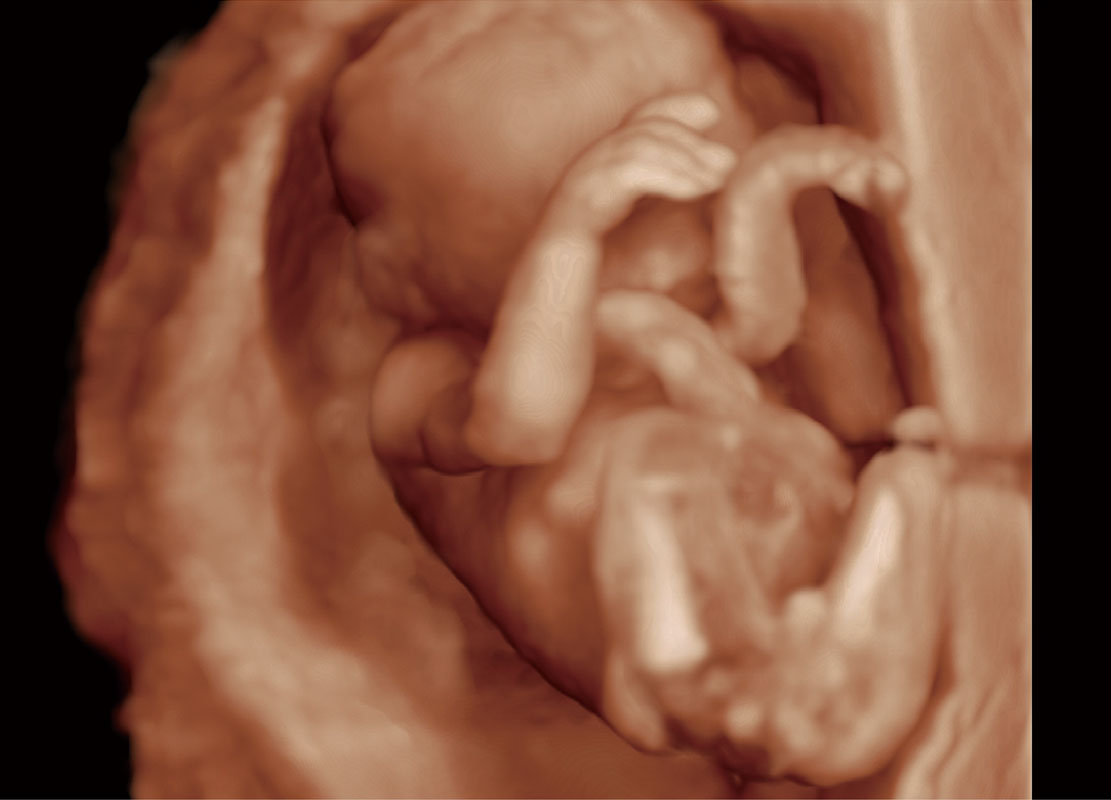

P60在胎儿早孕期超声筛查中为您带来优异的图像质量。

高分辨率容积成像-早孕胎儿